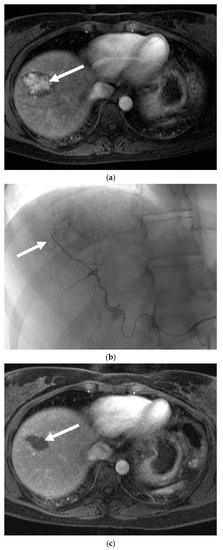

Six patients with 10 lesions were treated; imaging from one case is shown in Figure 3. Follow-up ranged from 0–69 months. Pain was a presenting complaint in three patients and five patients had a lesion greater than 5 cm in diameter. Two patients reported oral contraceptive use for greater than six months. Four of the six patients were treated with Embospheres and two were treated with PVA particles +/− ethiodol. The median change in tumor volume was −67.0% and ranged from −92.9% to +65.8%. The median volume changes for spherical particles (five lesions) and PVA (four lesions) were −77.9% and −15.1% respectively. As per RECIST, three lesions were stable, five had a partial response, and one had progressive disease. There was one confirmed complication of postembolization syndrome and one possible case of Staphylococcus bacteremia that was treated at an out of state hospital (SIR Adverse Event Severity Scale levels 1 and 4, respectively [13]). One patient was lost to follow-up and one patient had a subcapsular bleed in the region of the treated adenoma 49 months after the index procedure; it is uncertain if this represented a delayed bleed from the treated tumor or from a separate adenoma in the same region.

Figure 3.

Hepatic adenoma following embolization. (a) MRI with gadolinium shows an enhancing 4.3 cm lesion in segment 8 (solid white arrow). This was symptomatic and had increased in size over the past year. (b) Selective injection of the right hepatic artery demonstrating the hypervascular hepatic adenoma (solid white arrow). This was treated with 40–100 µm and 100–300 µm tris-acryl gelatin microspheres. (c) Three months following embolization, MRI with contrast shows complete necrosis of the adenoma with interval decrease in size (solid white arrow).